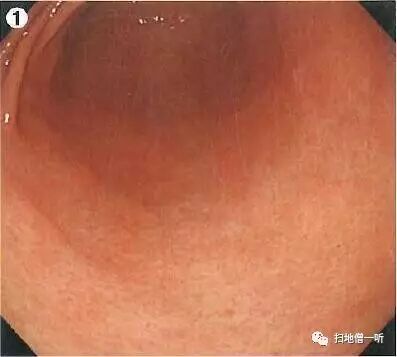

患者为一60岁女性,因进食后胃痛行胃镜检查,无HP除菌史,碳呼气试验阴性,血清学HP抗体阴性。

Q:胃癌在何处?

提示:注意退色调粘膜表现